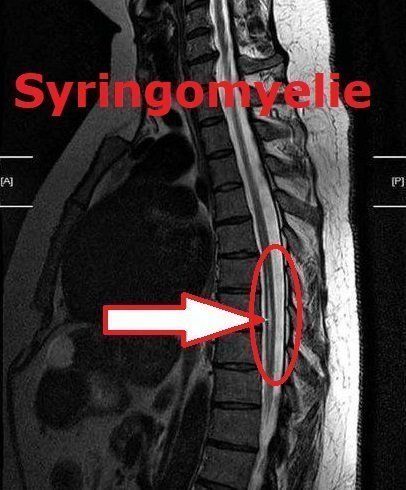

Syringomyelie

MRT Aufnahmen:

Syringomyelie & Chiari Malformation